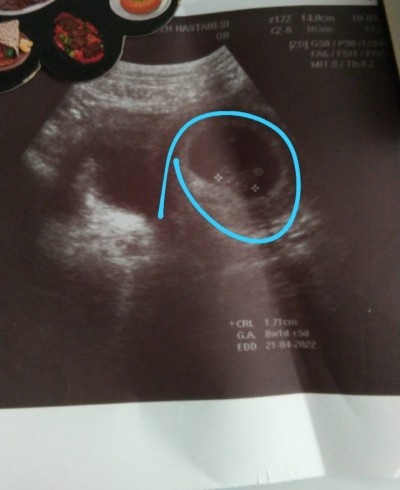

Kızlar kese şekline göre cinsiyet tahmini yapabilir misiniz acaba 8 haftalık bir ultrason fotosu var da

Benim şimdi nerde anlamadim pek sağ mi solmu kağıda göre

Sol galiba csnim aman bosver kiz hic inandirici gelmedi  keseye gore cinsiyet belli olsayfi ilk haftalardan doktorlar bilirlrr